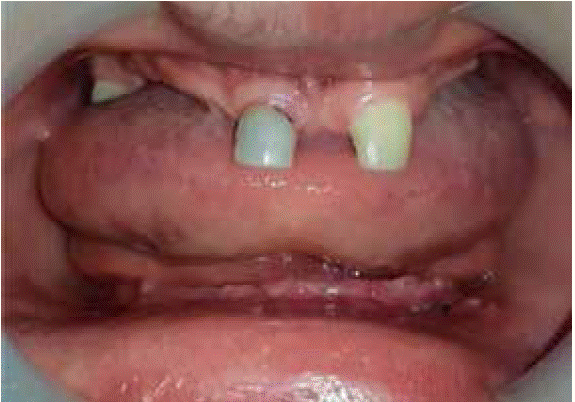

Al examen estomatológico se observa atrofia ósea de los procesos alveolares en ambos maxilares, se destaca anodoncia verdadera de OD # 11, 12 ,13, 14, 15, 16, 18, 22, 23, 24, 25, 26, 27, 28, 31, 32, 33, 34, 35, 36, 37, 38, 41, 42, 43, 44, 45, 46, 47, 48, presencia de órgano dentario deciduo 51 con forma cónica y movilidad, además sobreinserción del frenillo labial superior. Los rebordes alveolares del maxilar superior e inferior se disponen como clase III según la clasificación de Seibert. Se diagnosticó gingivitis marginal leve asociada a placa bacteriana generalizada (Figura 2).

Radiográficamente se observaron colapsos de reborde superior e inferior clase III según la clasificación de Seibert, presencia de un resto radicular a nivel de OD 43 y zonas radiopacas a nivel del 51 compatible con obturación (Figura 3).